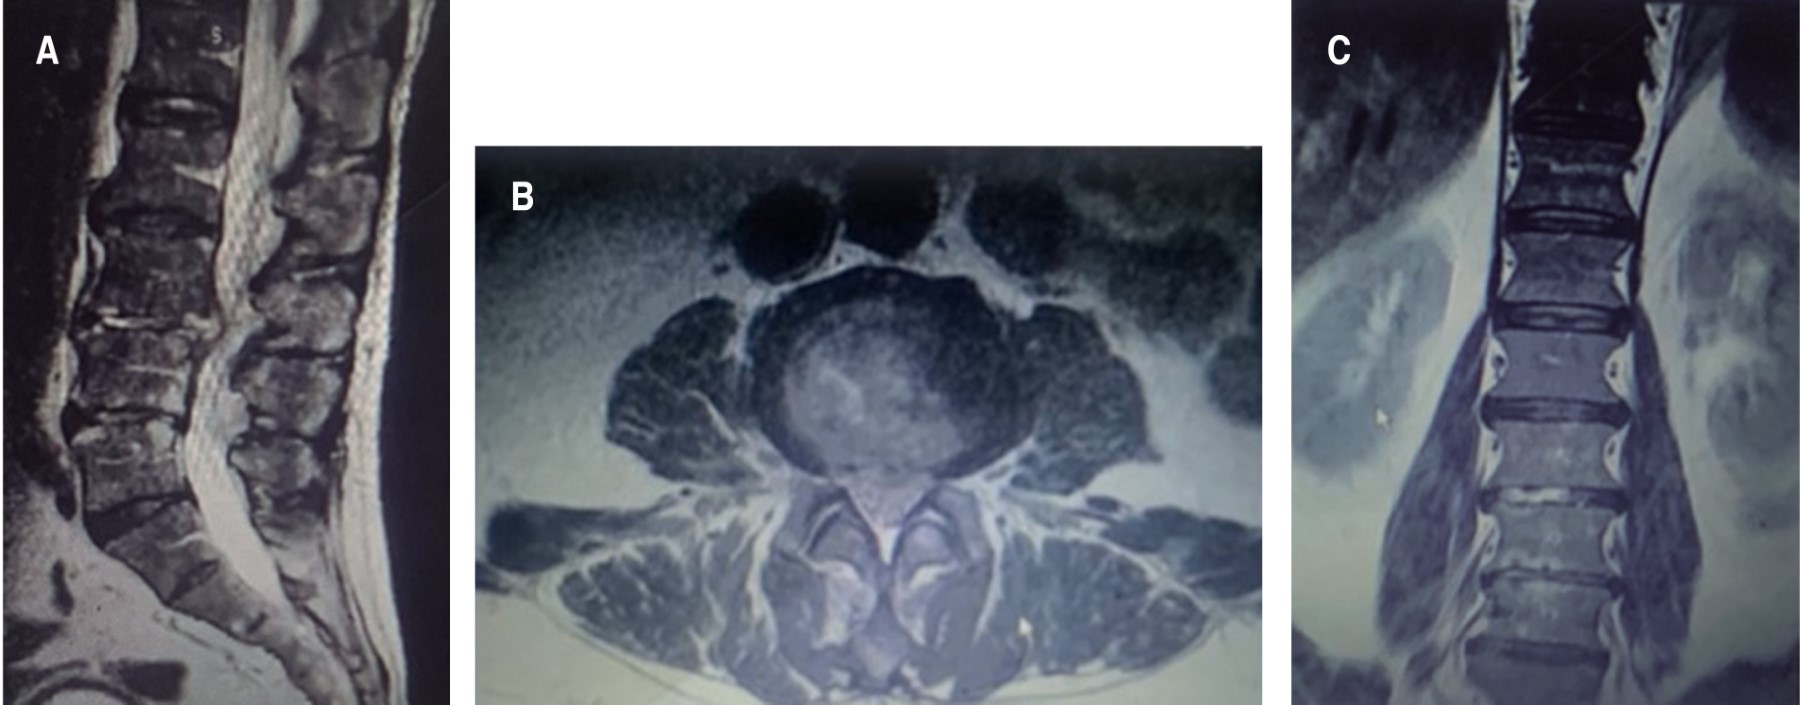

Figura 2